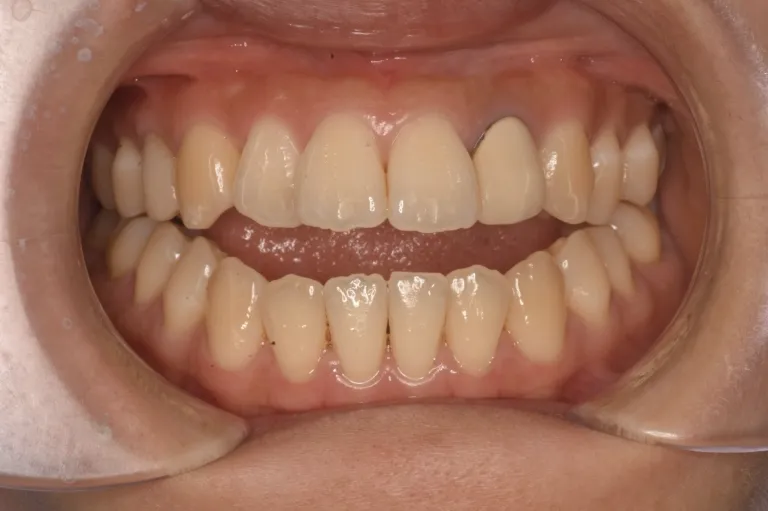

• 治療後

治療後

患者さんのお悩み、希望 前歯がまったく噛み合わず、食べ物を前歯で噛み切れないことに悩まれていました。滑舌にも影響があり、日常生活上のストレスが大きくなっていました。地元の矯正歯科では「外科手術が必要」と診断されましたが、できれば手術を避けたい、そして目立たない方法が良いというご希望がありご来院いただきました。

治療方法 インビザラインを用いたマウスピース矯正を行いました。 アタッチメントあり、顎間ゴム使用。 通院頻度:5ヶ月ごと ※症例により異なります

治療期間 1年4ヶ月(通院頻度5ヶ月に1度程度)※症例により個人差があります 手術なし、マウスピース矯正のみで開咬の改善が可能でした。

患者さんの感想 地元の歯医者では手術をしないと治らないと言われたオープンバイトでしたが、インスタグラムでこちらの歯科で私と同じ症例をマウスピースで矯正されていたのでこちらを選びました。無料相談から丁寧にしていただき、治療計画も分かりやすかったです。遠方から来ていたこともあり、5〜6ヶ月に1回の来院で良いように調整してくれたので、続けやすかったです。治療も思った以上に早く終わり(約1年半)、歯並びから噛み合わせまでしっかり調整してもらったのでとても満足です。